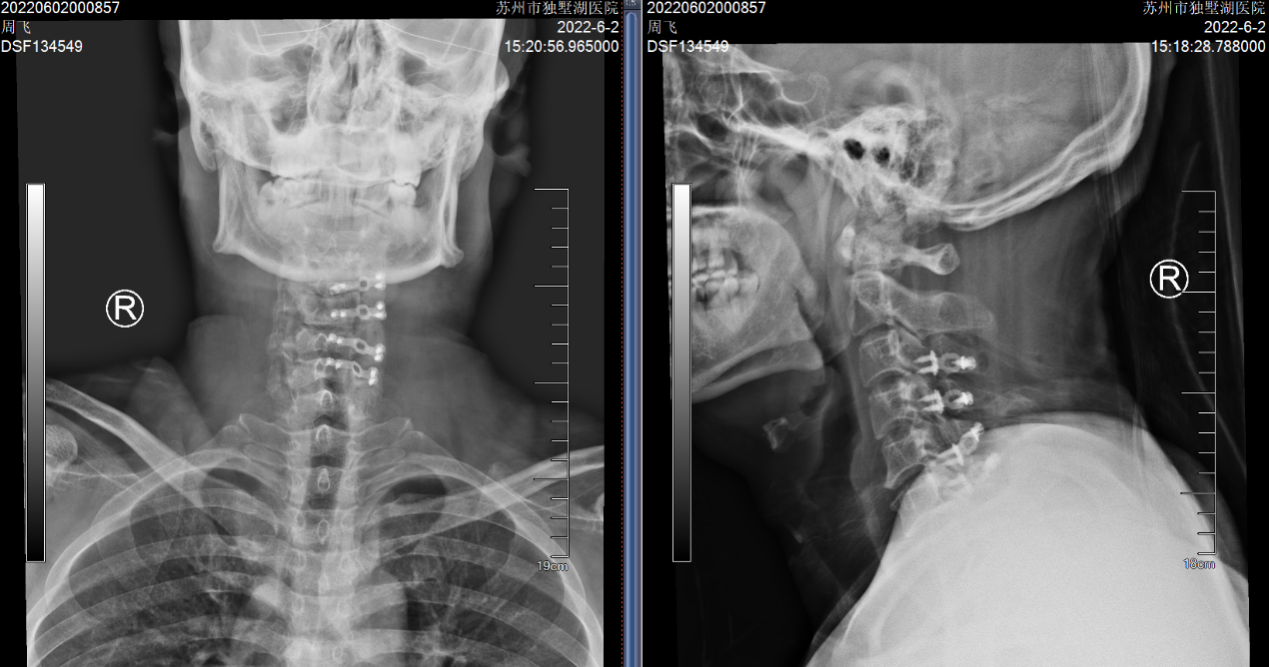

无独有偶,我院骨科还为一对姐弟完成了一组颈椎后路手术。姐弟俩吕艳、吕飞(化名)均患有“颈椎后纵韧带骨化症”。弟弟吕飞今年40岁,是位企业白领。别看他年龄不大,其实已多年饱受颈椎病之苦。由于长期伏案工作,这些年他常常感觉自己四肢乏力,走路像踩在棉花上一般,像系纽扣、写字这样的活动也逐渐无法完成,这让他很是着急。通过亲友介绍,他找到姜为民主任寻求帮助,姜主任在仔细的查体和阅片后,判断吕飞的颈椎后纵韧带骨化节段多,症状重,应当尽早手术,解除对脊髓的压迫。

(颈椎CT提示患者C3-6椎体后纵韧带骨化明显,椎管狭窄显著)

吕飞采纳了姜主任的建议,办理了住院,接受了“颈椎后路椎管扩大成形术”,就是脊柱外科医生俗称的“单开门”手术。该术式可以在扩大颈椎椎管空间,解除脊髓压迫的同时,最大程度地保留患者颈椎的活动度,避免术后颈部僵硬的情况发生。术后,吕飞的症状有了显著的改善,术后一周便顺利出院了,对此他感到非常开心。

(颈椎术后X片:C3-6椎管扩大成形术后)